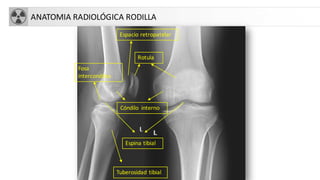

ANATOMIA RADIOLÓGICA RODILLA

Rotula

Espacio retropatelar

Cóndilo interno

Fosa

intercondilea

Espina tibial

Tuberosidad tibial

ANATOMIA RADIOLÓGICA RODILLA Rotula Espacioretropatelar Cóndilo interno Fosa intercondilea Espina tibial Tuberosidad tibial